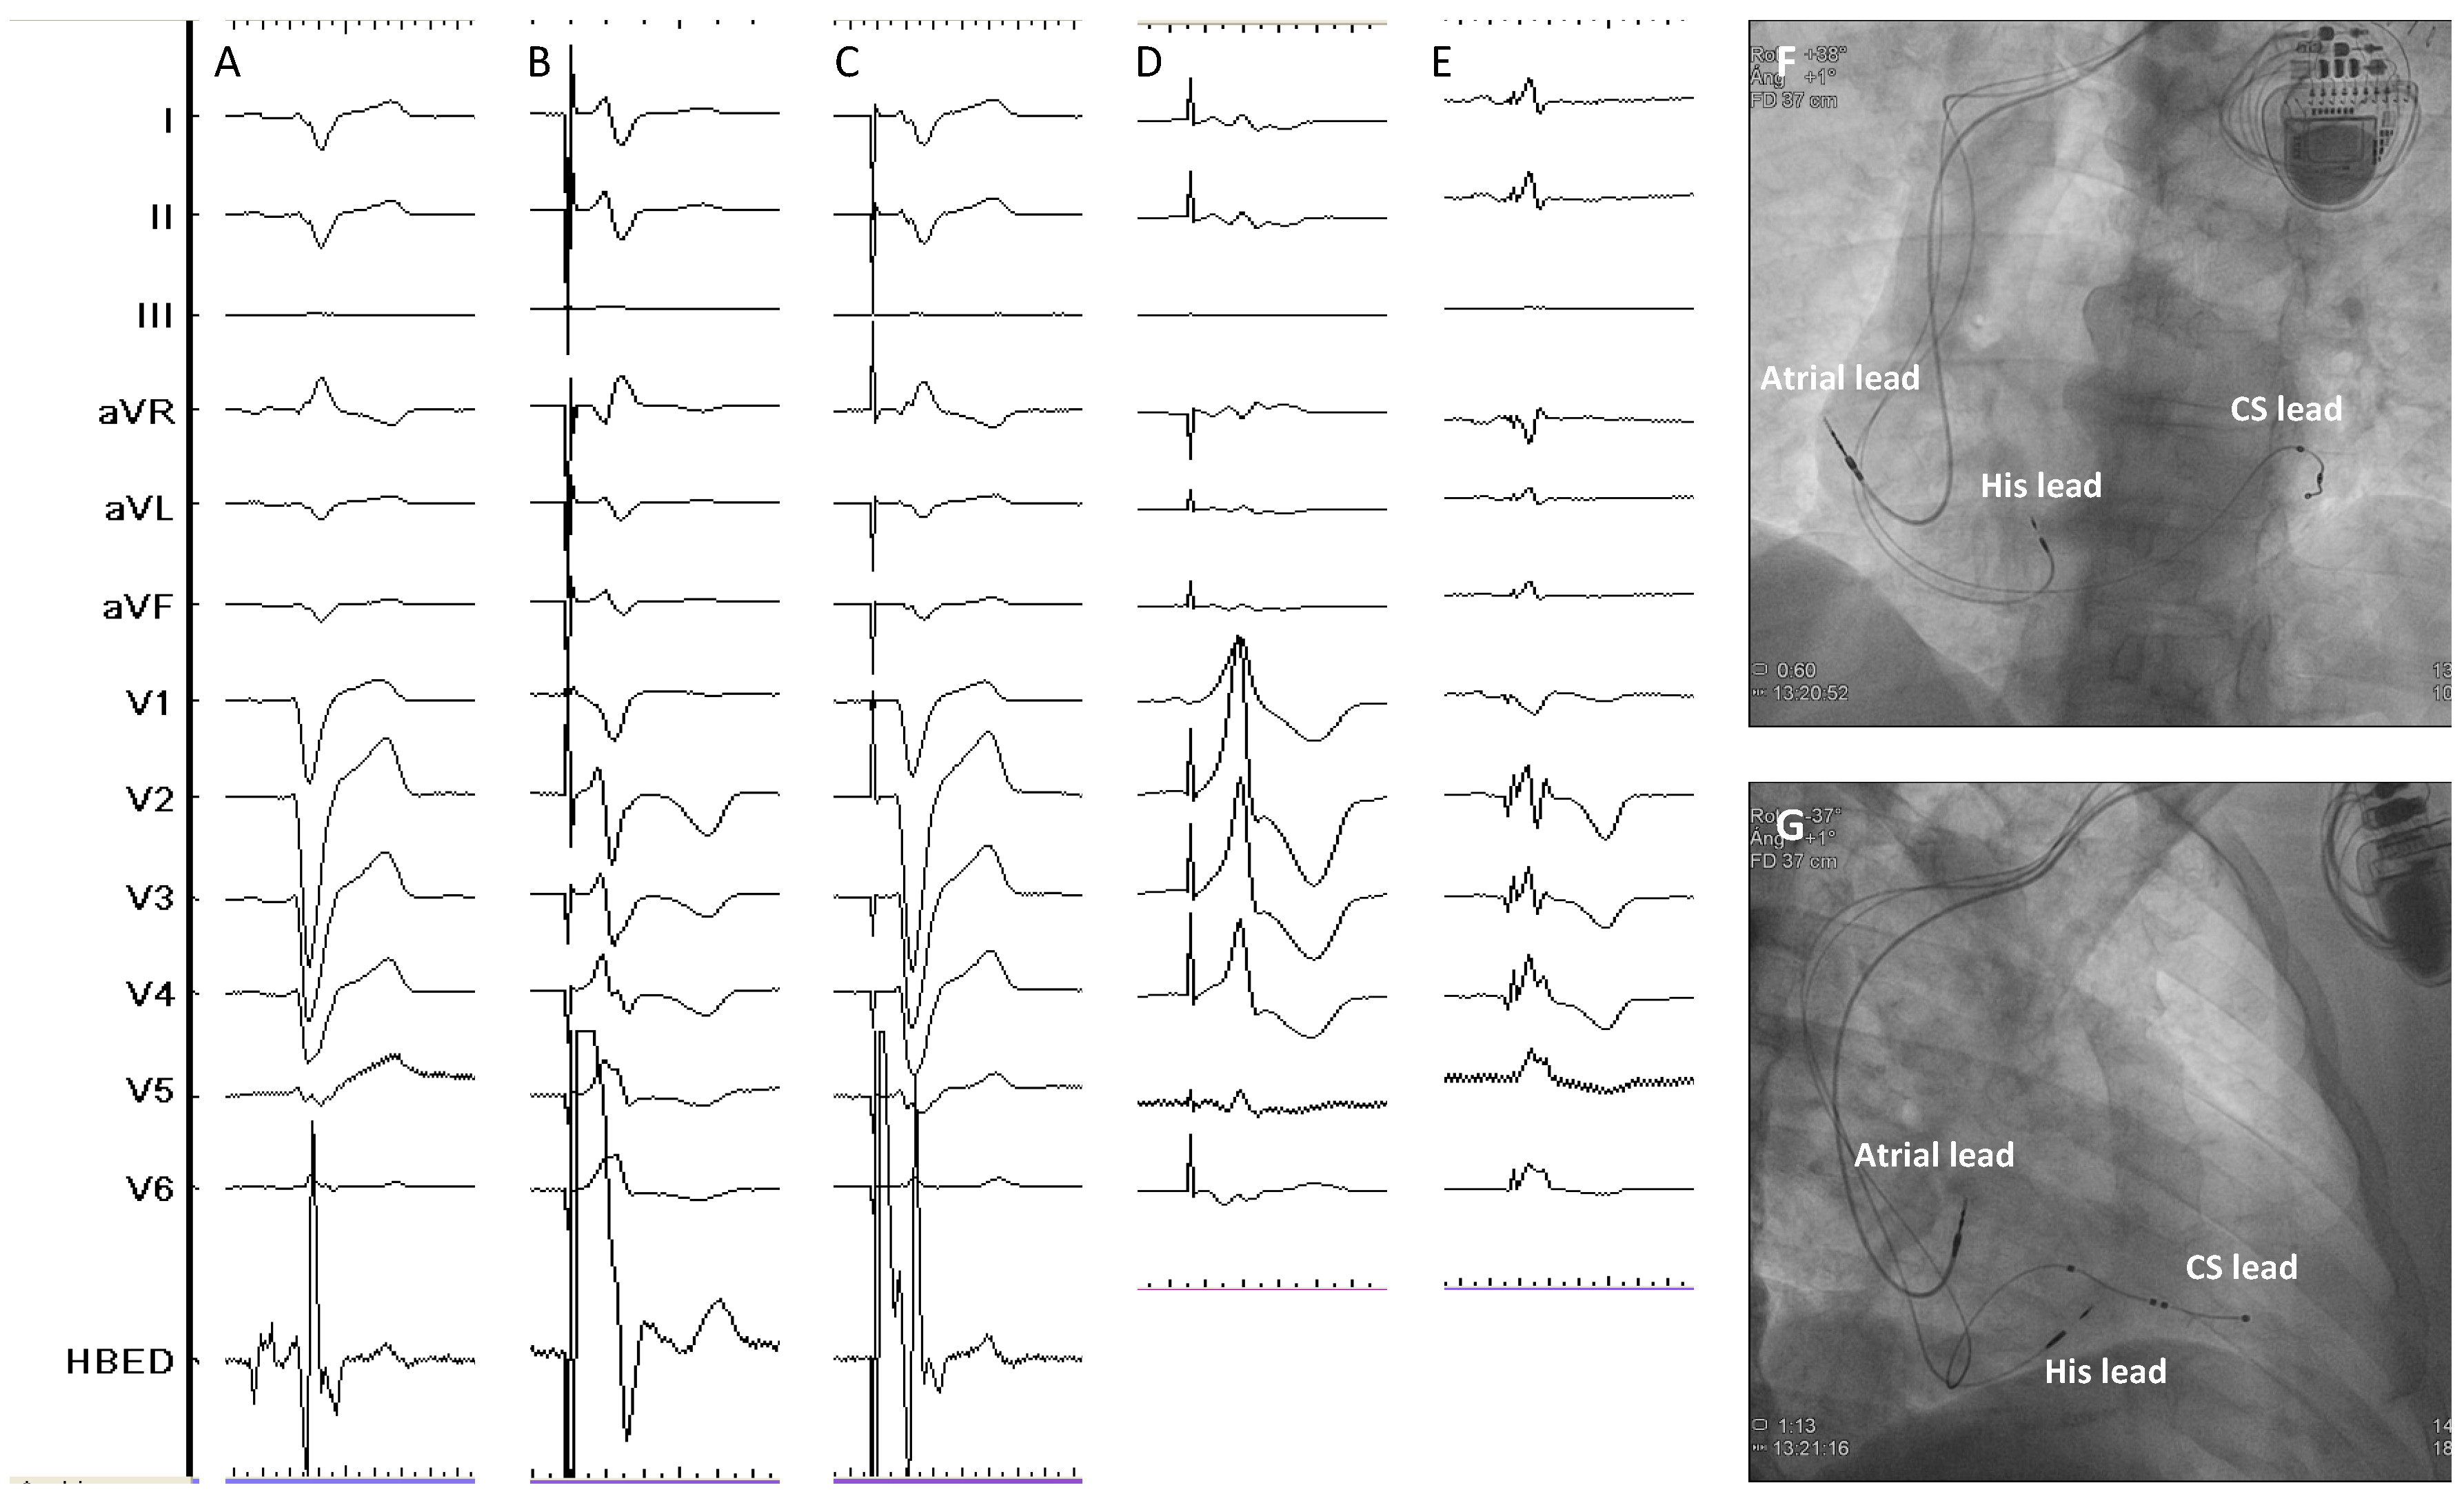

- Vijayaraman, P.; Herweg, B.; Ellenbogen, K.A.; Gajek, J. His-Optimized Cardiac Resynchronization Therapy to Maximize Electrical Resynchronization: A Feasibility Study. Circ. Arrhythm. Electrophysiol. 2019, 12, e006934. [Google Scholar] [CrossRef]

- Zweerink, A.; Zubarev, S.; Bakelants, E.; Potyagaylo, D.; Stettler, C.; Chmelevsky, M.; Lozeron, E.D.; Hachulla, A.L.; Vallée, J.P.; Burri, H. His-Optimized Cardiac Resynchronization Therapy with Ventricular Fusion Pacing for Electrical Resynchronization in Heart Failure. JACC Clin. Electrophysiol. 2021, 7, 881–892. [Google Scholar] [CrossRef] [PubMed]